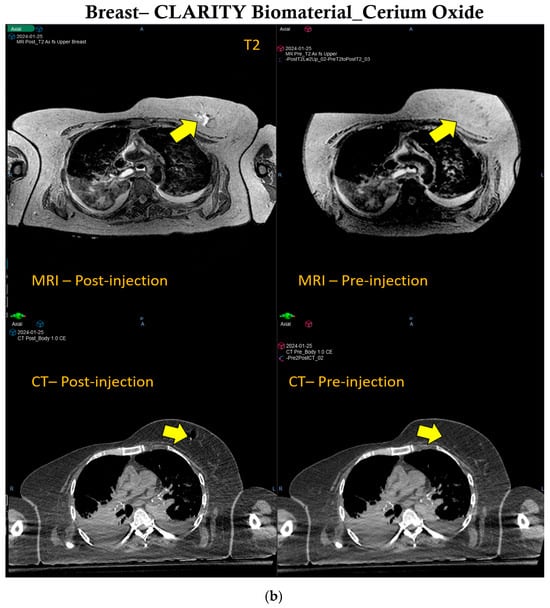

Manganese oxide offers significant multi-functionality in the CLARITY biomaterial, providing both CT and MRI contrast over time during radiotherapy. Figure 3 shows that the contrast provided by manganese oxide nanoparticles is brighter in MR images and lasts beyond the 30 days of observation, as opposed to the CT contrast provided by these same nanoparticles. However, Supplementary Figure S2 shows CT contrast for up to 30 days post-treatment. Human cadaveric specimens were used to further evaluate the CT and MRI contrast provided when the CLARITY biomaterial was formulated with Mn2O3 and injected into the right kidney of the specimen, as indicated by the yellow arrow shown in Figure 4a. CLARITY biomaterial formulated with cerium oxide interestingly also showed both CT and MRI contrast in the breast tissue of the specimen, as shown in Figure 4b. An additional functionality of the manganese oxide nanoparticles is the potential to address hypoxia, which is critical for enhancing radiotherapy and overcoming immunosuppression [28,29,30,31].

Figure 4.

IGRT capability of CLARITY biomaterial in Human Cadaver. (a) The right kidney of the human cadaver specimen is showing CT and MRI (T1-weighted) contrast after being inoculated with CLARITY biomaterial formulated with manganese oxide nanoparticles, as shown by the yellow arrow. (b) The breast tissue is showing similar CT and MRI (T2-weighted) contrast post-injection of the CLARITY biomaterial formulated with cerium oxide nanoparticles, as indicated by the yellow arrow.

2.6. MRI and CT Acquisition for the Human Cadaver

To further assess the feasibility of the CLARITY biomaterial in providing image guidance, contrast imaging was conducted in a human cadaver approved by the Johns Hopkins Institutional Review Board (IRB) under protocol # NA_00070589 (PI KD). The source of the human cadaver involved in our research is the State of Maryland Anatomy Board. As an academic center, we can send requests to get and then later return the cadaver from the State of Maryland Anatomy Board for medical education and research. Please see this link https://health.maryland.gov/anatomy/Pages/EducatorsResearchers.aspx (accessed on 25 July 2024) for more information. A refrigerated, unfixed cadaveric specimen was implanted in 2 regions: (a) the right kidney, with 3 mL of the CLARITY biomaterial formulated with manganese oxide nanoparticles, and (b) the breast, with 3 mL of the CLARITY biomaterial formulated with cerium oxide nanoparticles. CT simulation (TOSHIBA Helical CT scan with 2 mm slice thickness, 120 kVp, and X-ray tube current of 100 mA) was done with the cadaveric specimen in the supine position. The human cadaver specimen was subsequently imaged again. A Philips Achieva 3.0 T MRI System with BODY Transmit Coil was used for MRI acquisition with a repetition time of 5.31 ms, a flip angle of 100, a percent phase field of view of 70.833, and a slice thickness of 0.9 mm. CT and MR imaging were done before and after injection of the CLARITY biomaterial formulations.